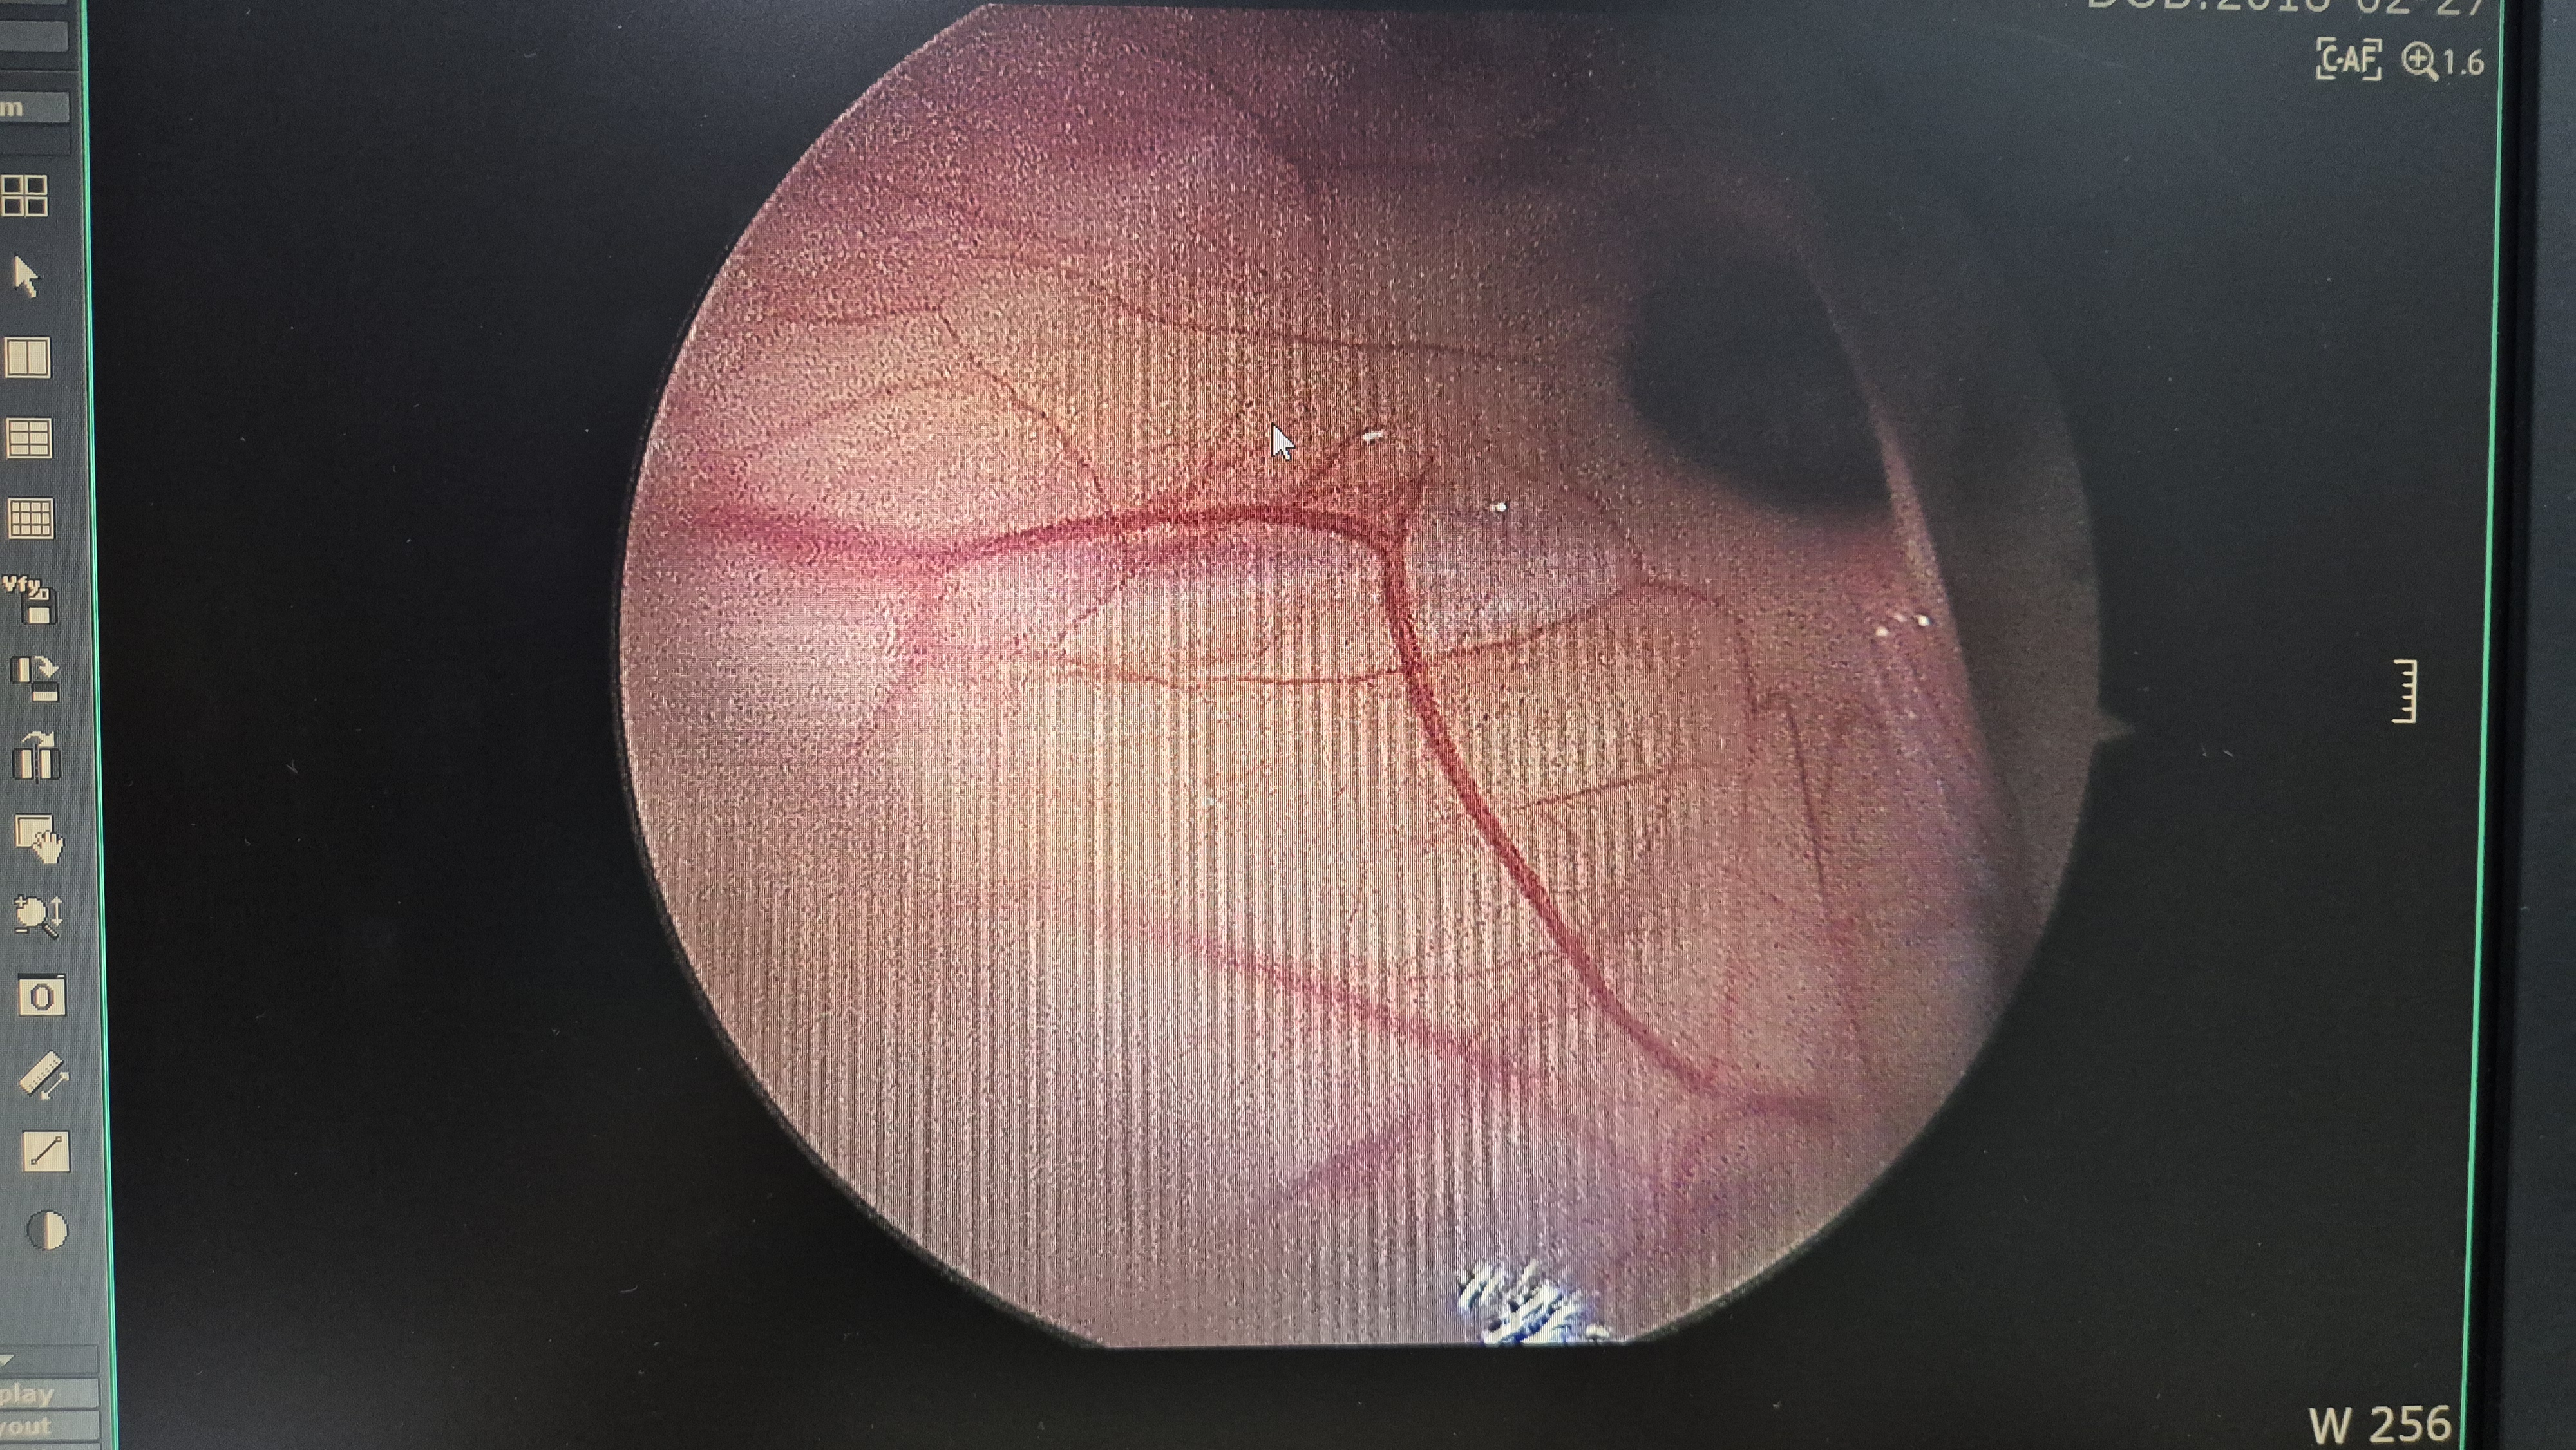

좌측 서혜부 탈장.

교정중.